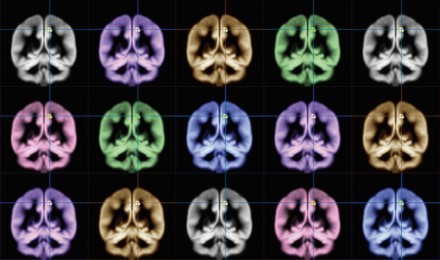

Resonancia magnética en mano, decidieron examinar el cerebro de los participantes en su investigación después de haberles pasado un test para conocer lo felices que eran habitualmente, la intensidad con que sienten las emociones, y cómo de satisfechos estaban con sus vidas.

Su análisis, publicado en “Scientific Reports”, reveló que quienes obtuvieron calificaciones más altas en las encuestas de felicidad tenían más materia gris en una zona del cerebro denominada precuneus, o precúneo. En otras palabras, esas personas que sienten una felicidad más intensa, la tristeza con menos intensidad, y son más capaces de encontrar sentido a la vida tienen precuneus grandes.

Situado internamente entre los dos hemisferios cerebrales, en la zona posterior, el precúneo es una de las regiones con mayor número de conexiones de la corteza cerebral, y actúa como un nodo logístico que permite el procesamiento de la información de forma consciente. Esta estructura es fundamental para manipular las imágenes mentales, está más evolucionada en los humanos que en el resto de los primates y otros animales y es una de las áreas del cerebro que más tardan en madurar (mielinizarse) en el cerebro en desarrollo.